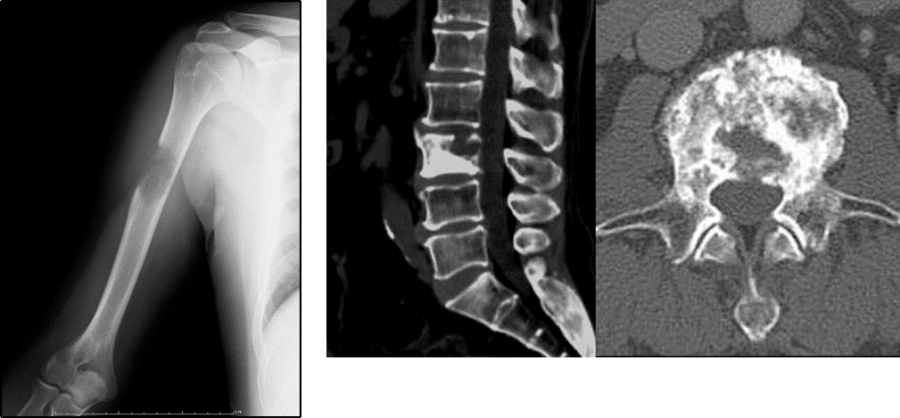

骨格系

骨は

1,750人の患者を対象とした2019年の研究によると、そのうち21%は骨転移のみで、全生存期間中央値は23.2カ月でした。